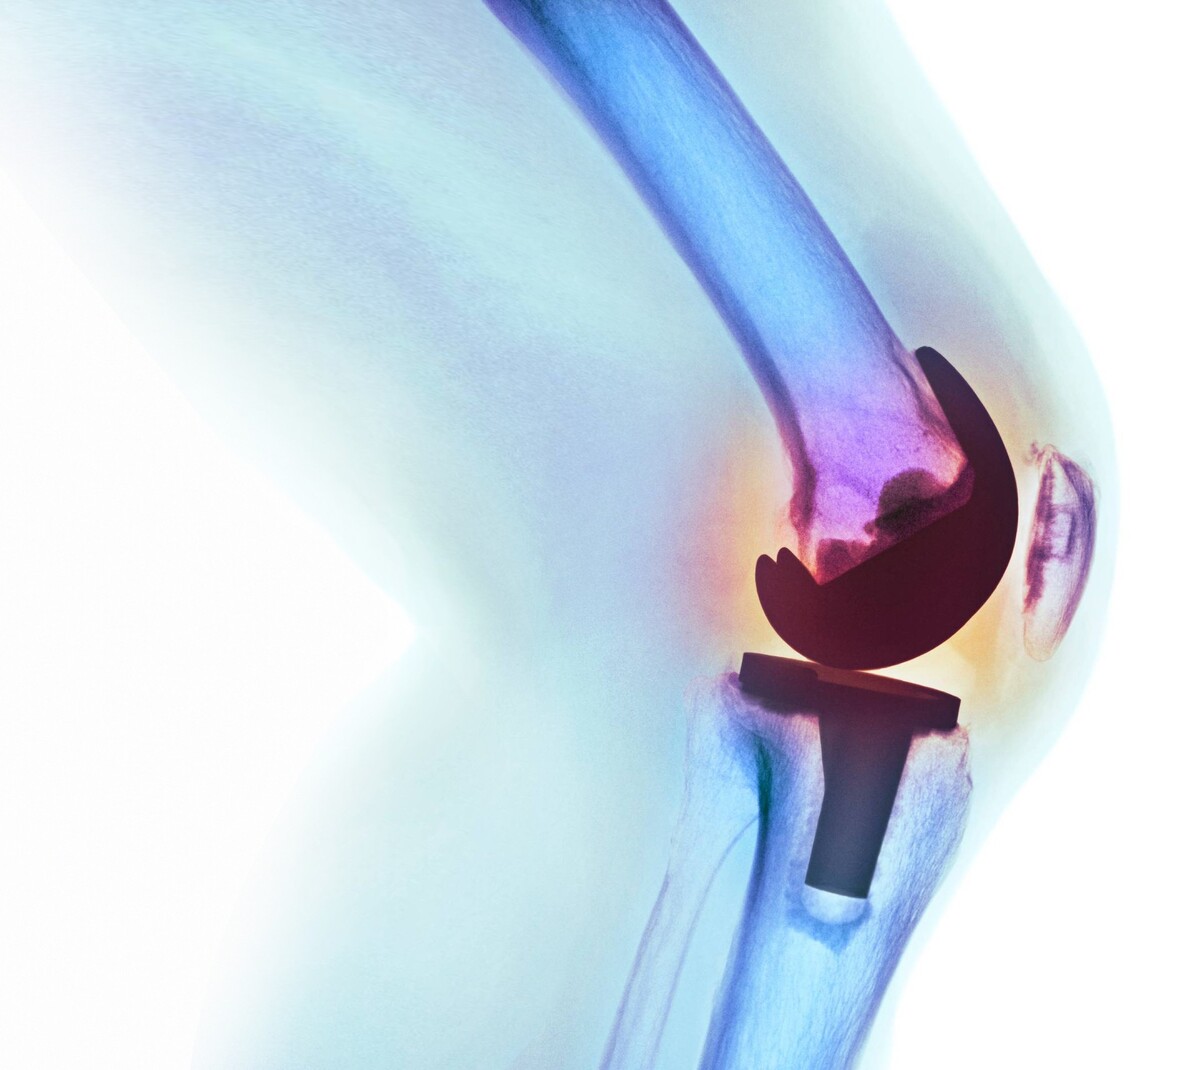

El reemplazo de rodilla es una cirugía que se realiza para cambiar partes de la articulación de la rodilla por partes artificiales nuevas. Es posible que una persona necesite un reemplazo de rodilla si tiene una lesión que cause dolor intenso y dificultad para realizar sus actividades diarias, como caminar y subir escaleras.

Este procedimiento es la opción cuando otros tratamientos no han tenido buenos resultados, y no han podido aliviar el dolor, o bien, si el desgaste de la articulación, ya es irreversible.

Las técnicas quirúrgicas innovadoras, como la cirugía asistida por robot, pueden mejorar la precisión de la cirugía de reemplazo de rodilla, con el objetivo de ayudar a los pacientes a recuperarse y ponerse de pie más rápido.

“Con la cirugía robótica, las sondas se colocan a través de clavijas en la tibia y el fémur. Estas sondas guían al cirujano en la realización de cortes precisos para restaurar la alineación y mejorar la función de la rodilla,” explicó el especialista.

La tecnología hace posible realizar una cirugía de reemplazo de rodilla con resultados potencialmente mejores para el paciente y una longevidad a largo plazo de los implantes de rodilla.

“La cirugía asistida por robot ofrece una mayor precisión para realizar procedimientos mínimamente invasivos con menos manipulación del hueso y potencialmente menos alteración del tejido blando,” agregó el Dr. Ali.